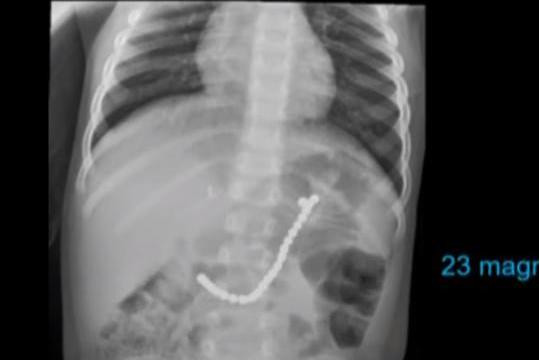

Chia sẻ với truyền thông, cô Nikki Cooke cho biết, con trai Caiden (2 tuổi) của mình đã phải nhập viện sau những hình ảnh chụp X-quang cho thấy, cậu bé đã nuốt 23 hạt nam châm vào bụng. Theo bà mẹ trẻ, khả năng cao là Caiden đã nuốt những hạt này khi đến thăm ông bà của mình.

| Hình ảnh X quang của Caiden. |